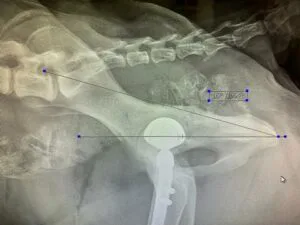

В 2021-2022 гг. — с соавторами разработал и запатентовал собственную систему для протезирования тазобедренного сустава V@Art (Виарт — https://v-art.info ). Данной системой пользуются ведущие врачи в России, а также в Белоруссии, Израиле, Кипре, Китае и Индии.

В октябре 2014 года сдал экзамене в Германии в GRSK на диагностику дисплазии тазобедренных суставов у собак. На сегодняшний день в России есть 2 практикующих специалиста, сдавшие экзамен на право диагностики дисплазии тазобедренных суставов, чьи заключения действительны в Европейских странах.

На 2020 год выполнил с коллегами больше всех в России операций по эндопротезированию тазобедренных суставов-операция, которая позволяет полностью восстановить опорную функцию тазовых конечностей у собак средних, больших и гигантских пород;